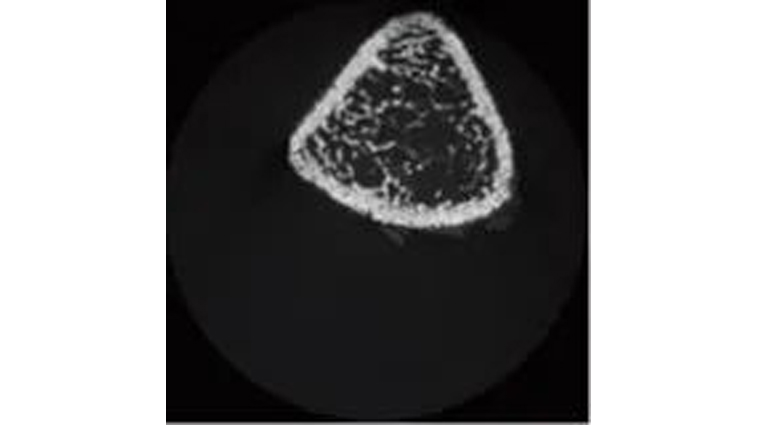

图4为骨骺的横断面图像,图5为骺端和干骺端横断面图像,图6为干骺端的横断面图像。在干骺端横断面上,圆形骨区为皮质骨,内部网状区为骨小梁。使用inspeXioSMX-100CT进行锥束扫描,一次即可获得区域内所有的横断面图像,还可以连续进行图像观察。

图6 干骺端CT图像